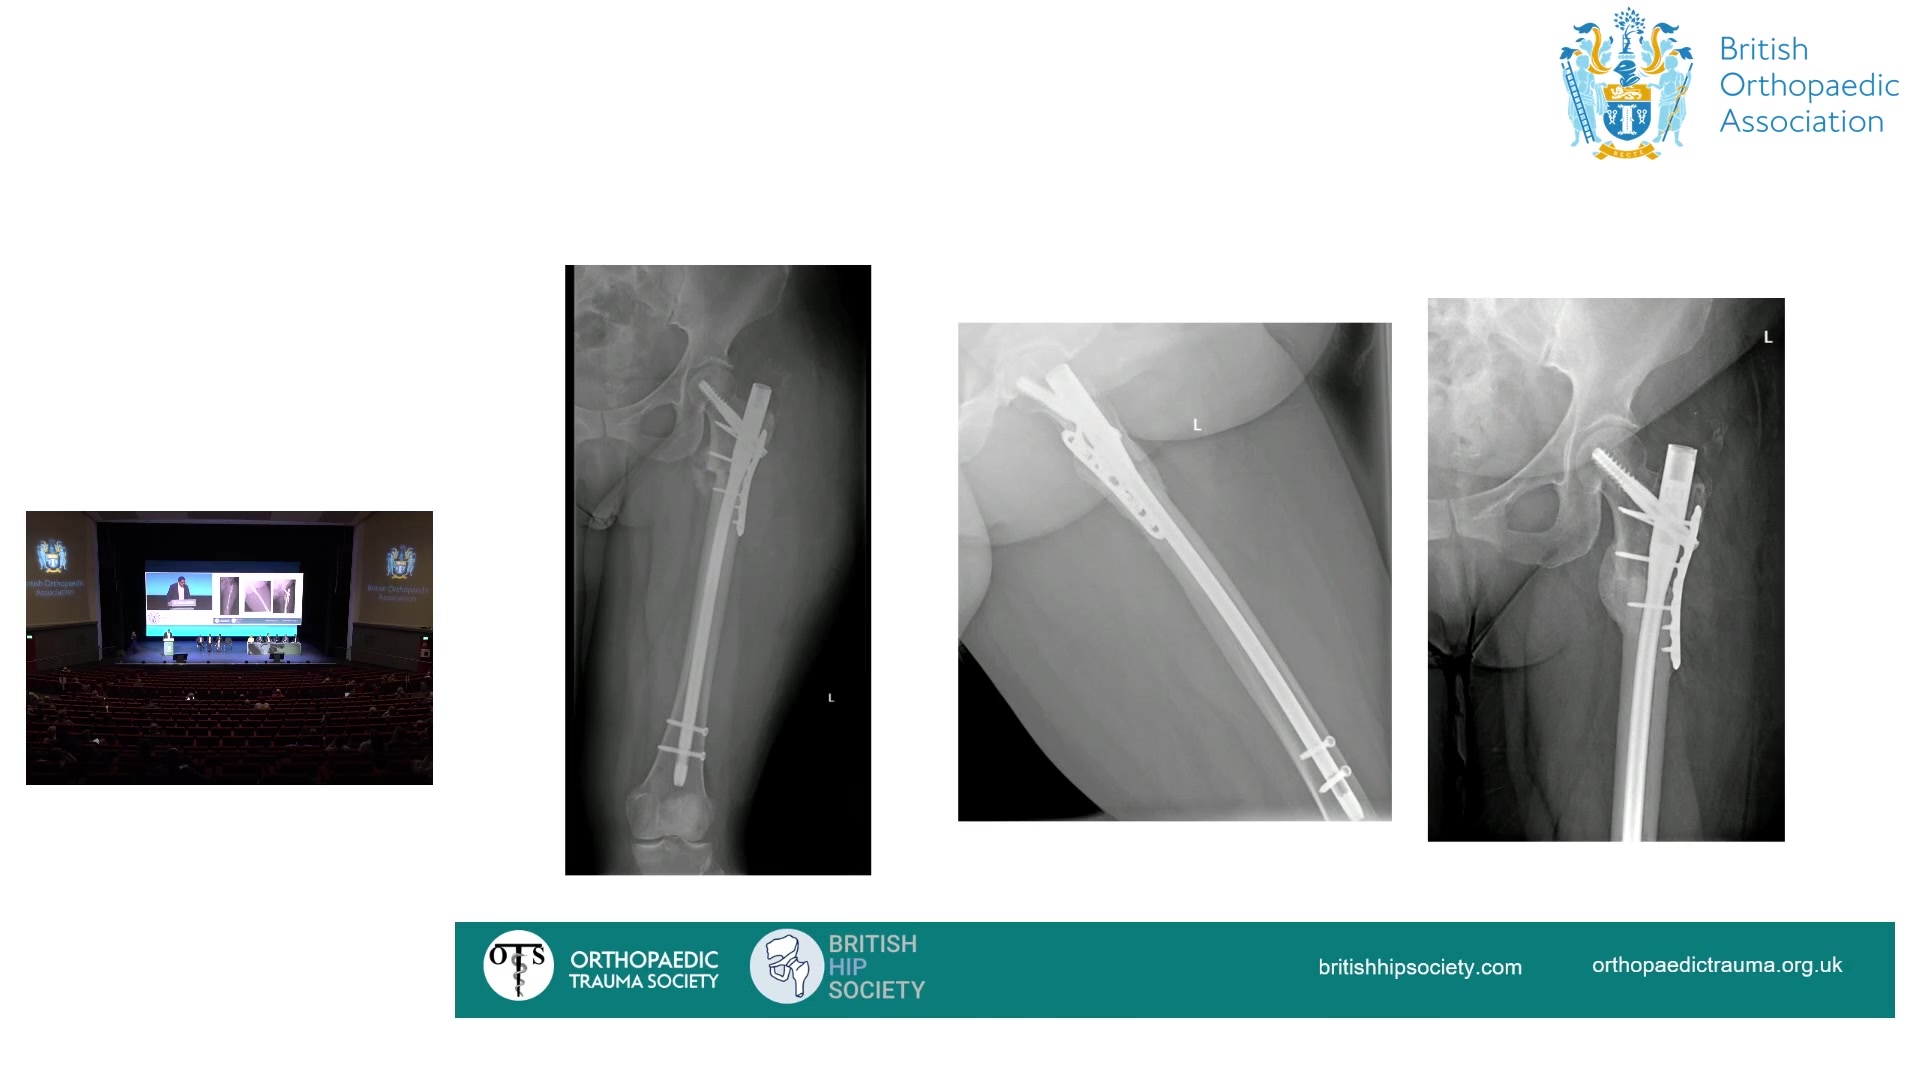

BHS & OTS Hip Trauma Revalidation Session - Case 3: Mr Jeya Palan